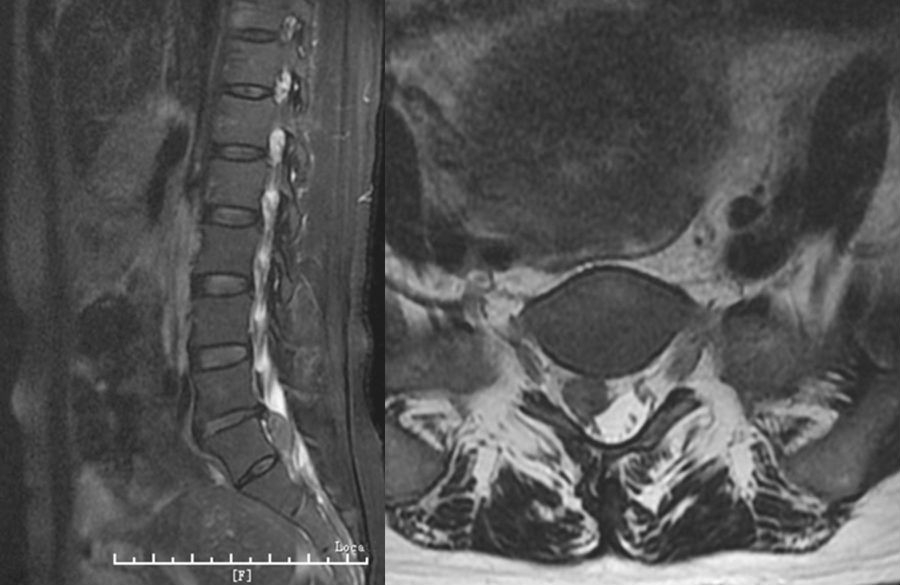

3. 脱垂游离型

破裂突出的椎间盘组织或碎块脱入椎管内或完全游离。此型容易导致马尾神经症状,常需手术治疗。(图2)

图1 腰椎磁共振显示中央突出型的L4-5椎间盘

图2 腰部磁共振显示脱垂游离型的L5-S1椎间盘